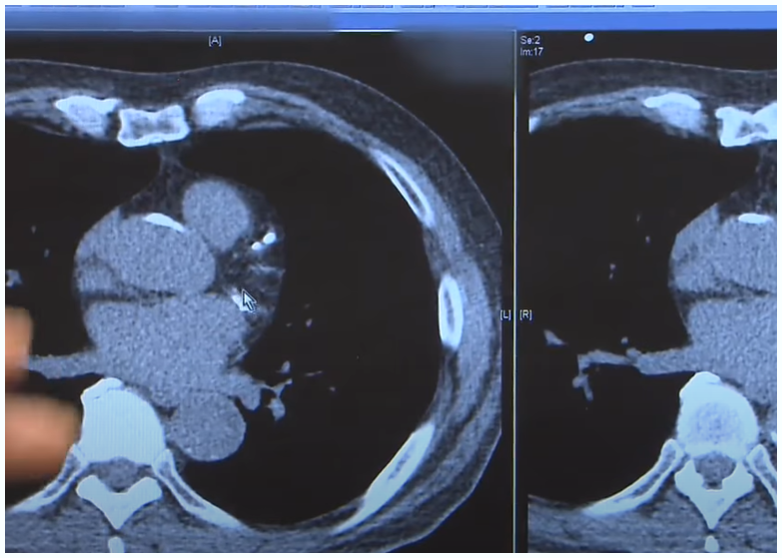

당뇨 어떤 병인가? 그리고 진단방법

당뇨는 끊임없이 관리해주는 질병이며 당뇨 자체적인 질병보다는 합병증이 위험한 병입니다 당뇨는 최대한 합병증의 발생을 늦추는 것이 치료의 목표이며 10~15년뒤에 합병증이 온다면 혈당관리를 해서 20~30년 으로 늦추는것이 목표입니다

당뇨는 한자풀이를 보면 소변에 당분이 섞여 나오는 증세입니다 전체 당뇨병의 90% 는 2형당뇨이며 1형당뇨는 급성에 2형당뇨는 만성에 초점을 맞춥니다 특히 1형의 환자들은 급성 케톤산혈증이나 초속효성 인슐린으로 인한 저혈당 쇼크를 조심해야 합니다

2형 당뇨병 환자는 관리를 하게되면 최대한 합병증을 늦출수 있습니다  당뇨는 인슐린 분비 기능에 문제가 생기는 대사질환입니다 1형과 2형을 구분하며  인슐린은 체내혈당을 에너지로 전환해 강하시키는 작용을 합니다

1형은 인슐린 분비가 정상적으로 이루어지지 않는경우이며 2형은 인슐린이 정상적으로 분비가 되지만 수용체에 문제가 생겨서 혈당제어 능력을 잃어 혈당 포도당의 농도가 높아지는것을 말합니다

혈당치는 정상인의 경우 70mg/dL~110mg/dL 수준이며(WHO기준), 식사로인해 당분을 섭취하여도 120mg/dL 이상으로는 올라가지 않는 것으로 알려져 있습니다 범위를 초과하는 경우 내당능장애 및 당뇨 진단이라고 측정합니다